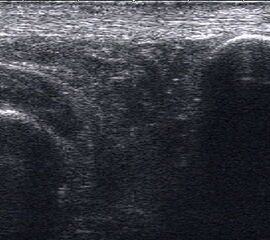

Tendopathien der Flexorensehnen

Dorsaler TS hinter dem Innenknöchel.

Abbildung 46

Lagerung: Rückenlage, Außendrehung des Beines.

Schnittführung: TS und LS hinter dem Innenknöchel beginnen und bis zum Os cuneiforme mediale fortführen.

Referenzstrukturen: Innenknöchel, Talus, Os naviculare, Os cuneiforme mediale, Sehnen der Mm tibialis posterior, flexor hallucis longus, flexor digitorum.

Befunde: Häufig betreffen die Pathologen die Tibialis-posterior-Sehne, die als erste Sehne hinter dem Innenknöchel zur Darstellung kommt. Halo-Phänomen und echoarme Verdickung bei akuter Tendinopathie, zunehmend inhomogen und echogen mit Kaliberschwankungen bis hin zu Teilrupturen bei Chronifizierung 5. Für die Erkennung von Teilrupturen sind TS in verschiedener Höhe besonders wichtig. Bei komplettem Riss mit Retraktion im LS Bild wie Spargelspitze mit umgebender Flüssigkeit oder Hämatom. Ein Os tibiale externum erscheint als echoreiche Struktur im Verlauf der Tibialis posterior Sehne mit dorsaler Schallauslöschung. Ein Os naviculare cornutum imponiert als starke Prominenz im Ansatzbereich der Tibialis posterior Sehne.